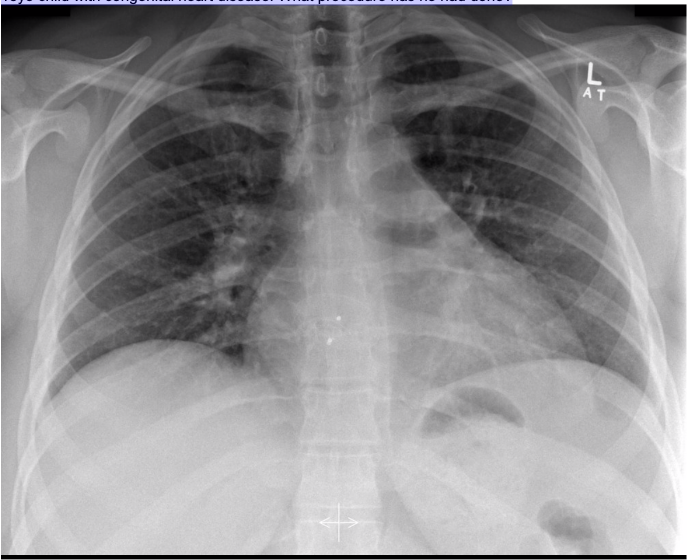

20.1 What is the abnormality in this CXR?

c. Pneumonia

Complete white-out of left lung with air bronchogram sign consistent with total consolidation. Patchy areas of ground glass opacities in right lung. There is silhouetting of the left heart border and left hemi-diaphragm. There is no rib crowding to suggest atelectasis.

Complete white-out of the hemithorax with air bronchograms and trachea in a central position is consistent with consolidation secondary to pneumonia. The patient is on linezolid, micafungin, and piperacillin-tazobactam pending culture and susceptibility studies.

Differential diagnosis of hemithorax white-out with a midline trachea include:

- consolidation

- pulmonary edema/ARDS

- pleural mass

- chest wall mass